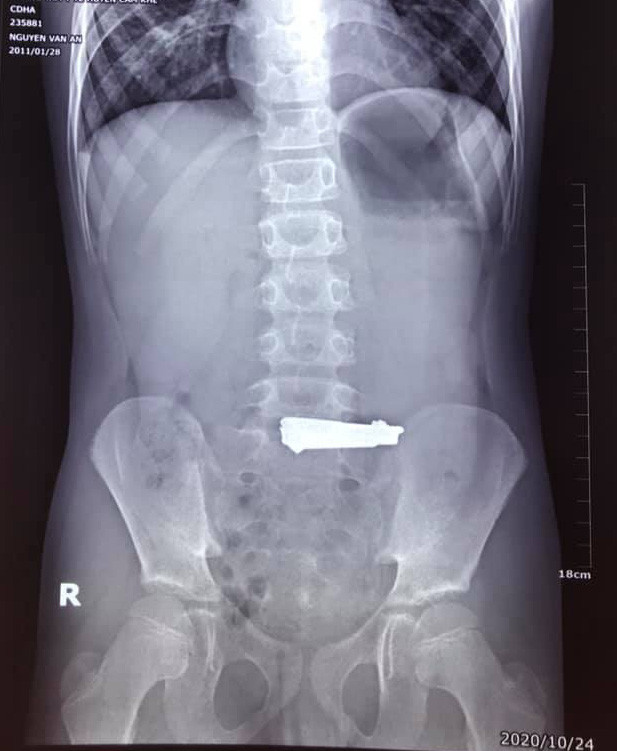

Vị trí của chiếc bấm móng tay trong cơ thể cháu bé 9 tuổi.

Như VTV đưa tin, sau khi tiến hành nội soi dạ dày, các bác sĩ phát hiện một chiếc bấm móng tay có kích thước 60x16mm nằm tại vị trí phình vị lẫn vào thức ăn khiến niêm mạc dạ dày bị tổn thương.

Xác định được vị trí dị vật, các bác sĩ nhanh chóng phẫu thuật, gắp thành công chiếc bấm móng tay ra ngoài. Qua lời kể của người nhà bệnh nhi cho hay, nguyên nhân của việc này là do cháu bé bắt chước làm theo video hướng dẫn nuốt bấm móng tay trên Youtube.